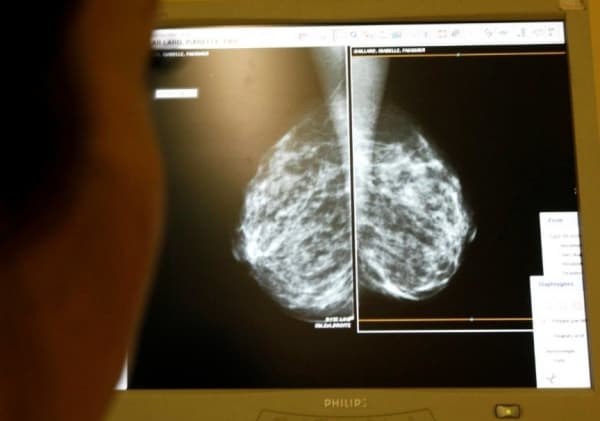

يمكن أن تساعد الفحوصات والفحوصات المنتظمة لأمراض النساء أيضًا في الكشف المبكر.